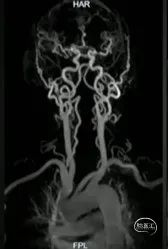

术前影像

· 患者三型弓,奇大脑前A3段动脉瘤,形态极不规则,血管入路极其迂曲

· 从大脑前动脉瘤起始段,有广泛伴有动脉粥样硬化的斑块

· 病变远端处于奇大脑前动脉双分叉位置,远端支架可着陆的空间较短,远端血管较细,且伴随斑块